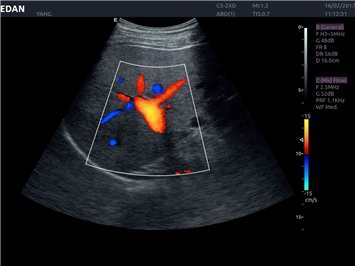

EDAN Acclarix LX4 представляет собой инновационную ультразвуковую систему, построенную на усовершенствованной платформе Acclarix. Сочетание высокого качества визуализации с интеллектуальным рабочим процессом делает эту систему оптимальным выбором для клиник, ценящих эффективность и экономичность.

Области применения:

Система Acclarix LX4 оптимально подходит для:

• Общей визуализации

• Акушерства и гинекологии

• Кардиологических исследований

• Сосудистой диагностики

• Педиатрии

• Исследования малых органов

Трехмерная реконструкция ЦДК:

Да

Энергетический допплер:

Цветовой допплер: